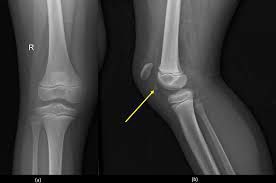

Platella fracture

A patella fracture is a break in your kneecap, the bone that covers your knee joint. It's usually caused by a traumatic injury, such as a fall or a blow to your kneecap. A patella fracture can be simple or complex. Some fractures require surgery to repair.